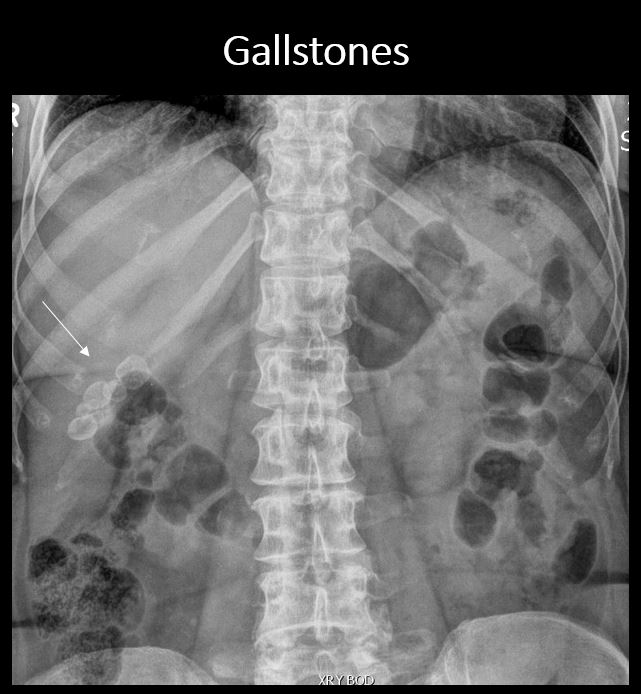

There is calcification in the expected region of the gallbladder. [Yes/No]